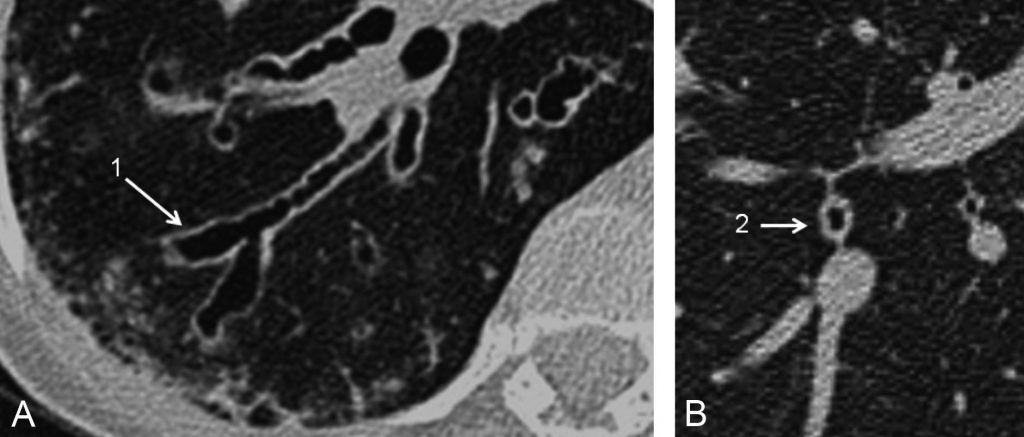

- les bronches sont bien identifiables jusqu’aux générations sous-segmentaires. Le syndrome bronchique se caractérise par un épaississement des parois bronchiques et une réduction de la lumière des bronches, plus rarement un aspect de bronchectasies cylindriques. Les bronchectasies correspondent à des bronches dont le calibre est supérieur à celui des vaisseaux satellites (figure 90.3).

Fig. 90.3 Scanner thoracique. Coupes axiales.

Coupe centrée sur une bronche de la pyramide basale droite (A) montrant des bronchectasies variqueuses (1) et (B) un important épaississement pariétal (2).

Source : CERF, CNEBMN, 2022.